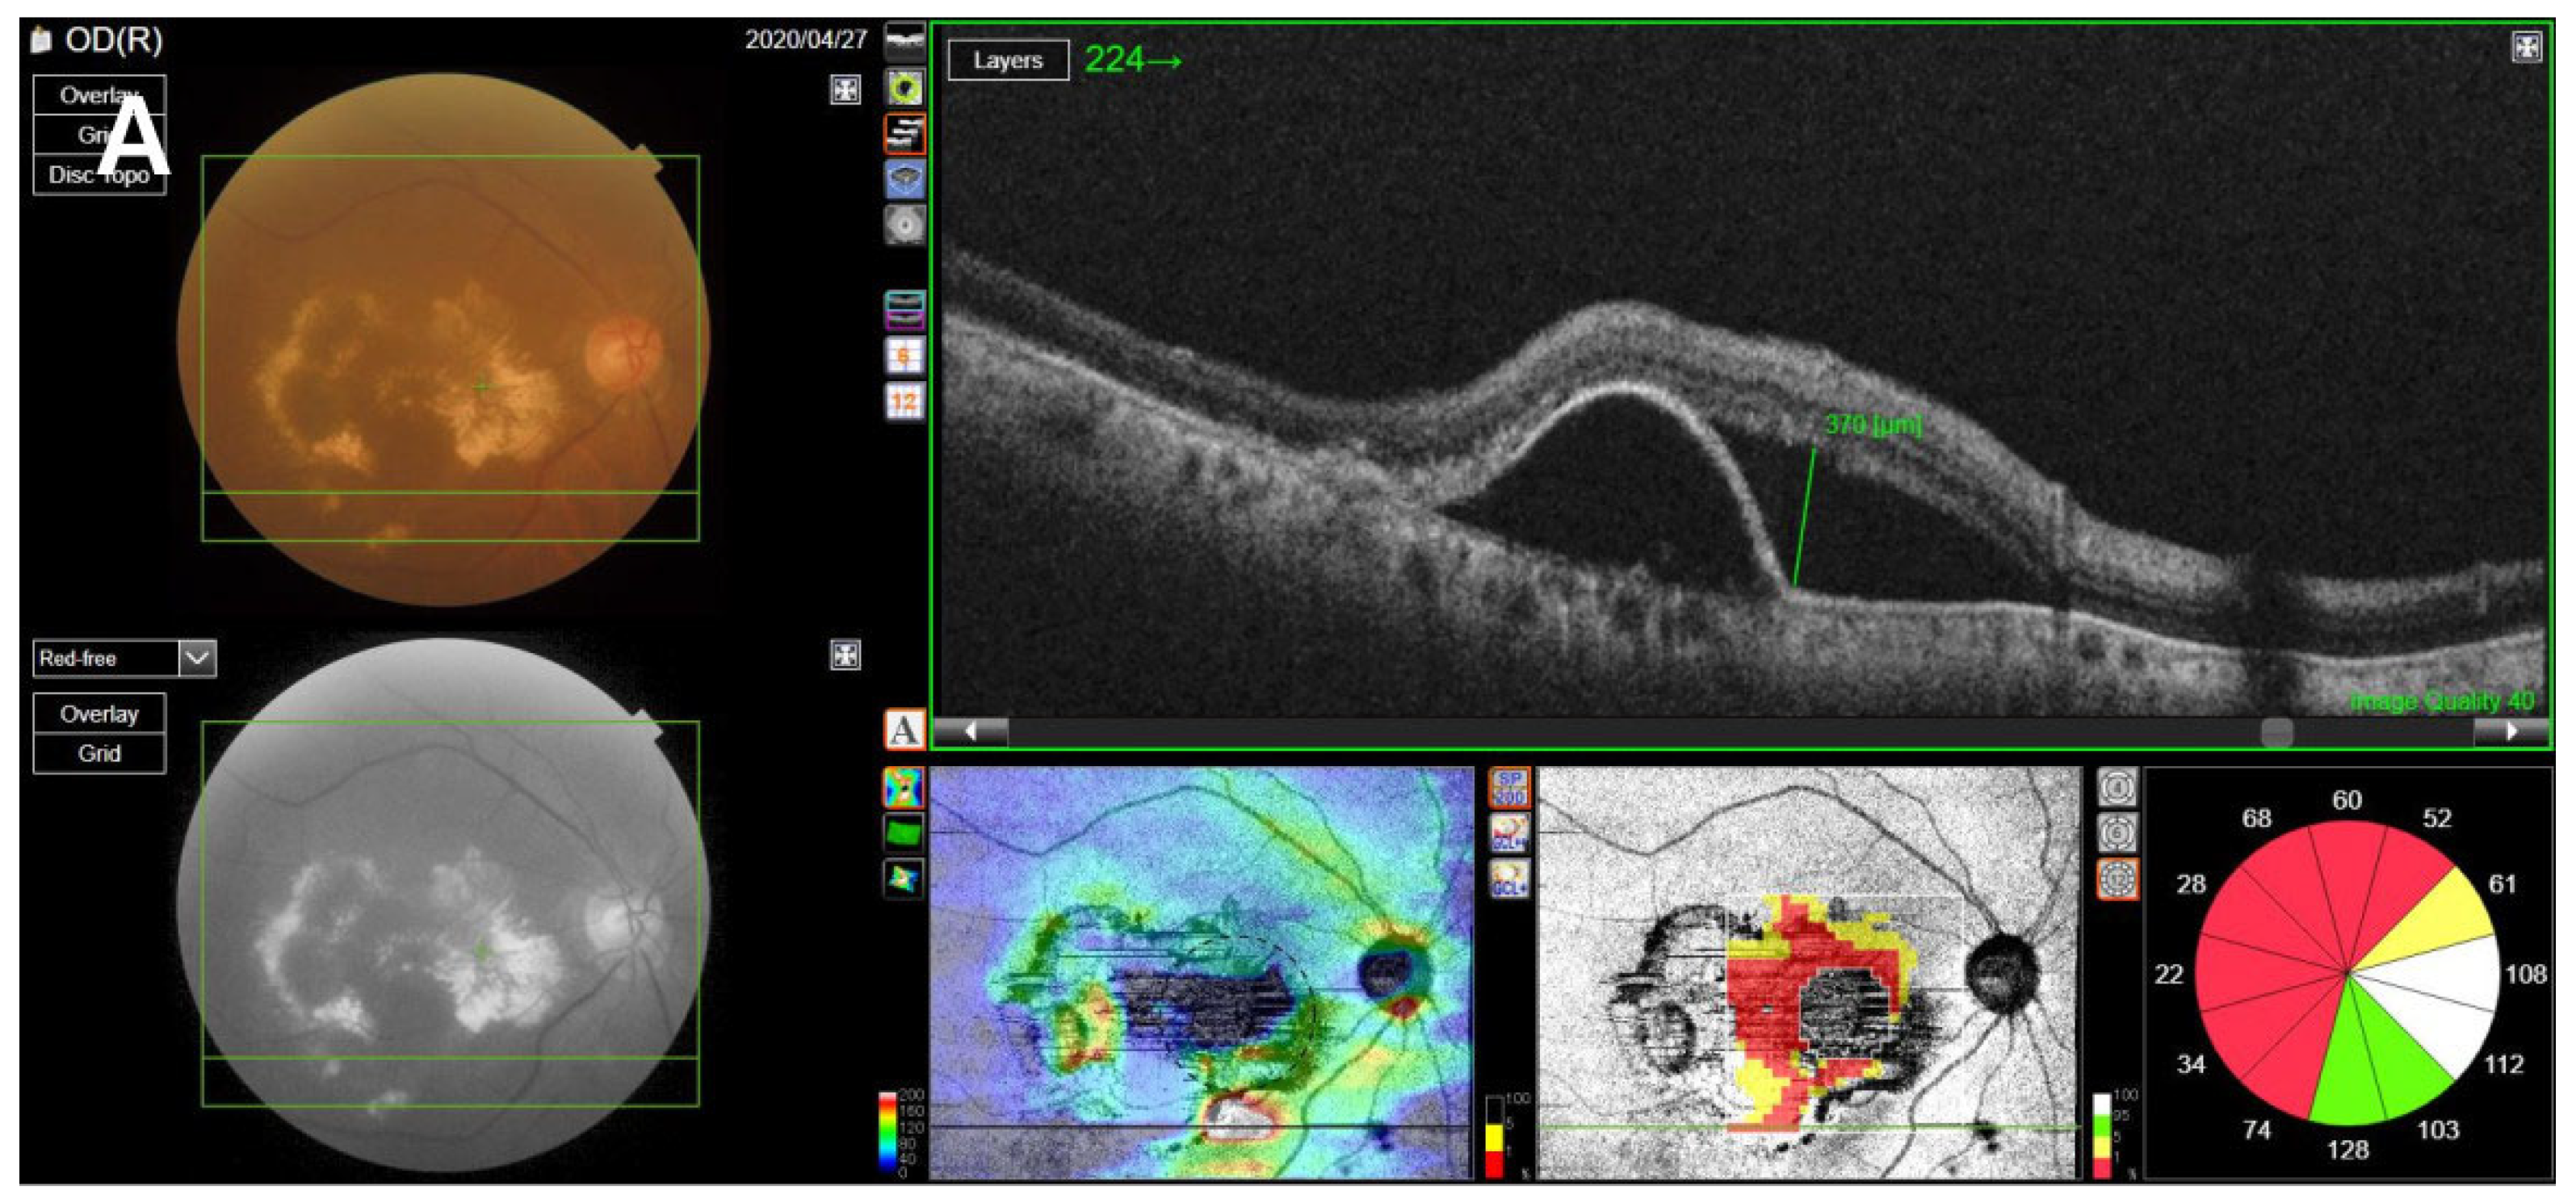

SS-OCT was performed on the enrolled eyes of all included patients using a swept-source DRI OCT Triton Plus (Topcon Co., Tokyo, Japan) at each follow-up point. Using the OCT scans, we recorded the central subfield thickness (CST) and any anatomical abnormalities including accumulated levels of subretinal fluid (SRF), intraretinal fluid (IRF), and subretinal hyperreflective material (SHRM) and presence of pigment epithelial detachment (PED), and measured the maximum height of the SRF and PED. CST, which refers to the average retinal thickness within a 1-mm-diameter ring based on the macula [19], was measured using built-in optical software (IMAGEnet 6 version 1.25.16650; Topcon Co., Tokyo, Japan). Anatomical abnormalities in OCT images, such as the levels of SHRM, SRF, PED, and IRF, were found to indicate exudative disease activity [20,21,22]. For patients with confirmed SRF accumulation or PED, the maximum SRF height (distance between the outer retina and the hyperreflective line of the RPE) was manually measured using the caliper tool in IMAGEnet software; a similar process was repeated to measure the maximum PED height (distance between the inner surface of the Bruch membrane and the outer surface of the RPE) by reviewing the OCT image [23,24] (Figure 1).

Figure 1.

Measurement of SRF, PED, SHRM, and IRF. (A) The maximum SRF height was measured as the maximum distance between the outer retina and the hyperreflective line of the retinal pigment epithelium on the OCT image, using the caliper tool using IMAGEnet software. (B) The maximum PED height was measured as the maximum distance between the inner surface of the Bruch membrane and the outer surface of the retinal pigment epithelium. (C) Presence of SHRM, which is a morphological feature seen on OCT as hyperreflective material located external to the retina and internal to the retinal pigment epithelium. (D) Presence of IRF, which appears as dark cystic accumulations of fluid above the outer plexiform layer. SRF, subretinal fluid; PED, pigment epithelial detachment; SHRM, subretinal hyperreflective material; IRF, intraretinal fluid; OCT, optical coherence tomography.

In anti-VEGF therapy, it is imperative to maintain an adequate injection interval to control disease activity [28,29]. Some studies evaluating the changes in intravitreal injection therapy during the COVID-19 pandemic have consistently shown that intravitreal injection was not administered on time during this period [12,13,14]. Yang et al. [14] reported that the BCVA of patients was worse during the pandemic period than before, and Sevik et al. [12] found that BCVA and OCT disease activity worsened in patients with a delayed injection after the end of the COVID-19 lockdown period. Although some studies have investigated nAMD patients with delayed treatment due to COVID-19, to our knowledge, this is the first study to evaluate the clinical prognosis, including the quantitative analysis of anatomical abnormalities, by tracking nAMD patients with delayed intravitreal anti-VEGF injections due to COVID-19 for up to 6 months after the delayed injection date. Borrelli et al. [30] tracked nAMD patients up to two consecutive follow-ups after the COVID-19 pandemic to evaluate the short-term changes in the clinical course of nAMD patients due to the spread of COVID-19. They found that the follow-up interval increased due to COVID-19, the BCVA worsened, and the longer the visit time was delayed, the worse the BCVA. Similarly, in this study, BCVA significantly worsened after the COVID-19 outbreak compared to before the outbreak, but no association was observed between the injection delay time and the degree of BCVA deterioration. Elfalah et al. and Naravane et al. [15,16] compared the BCVA and CST before and after treatment delay in patients of various disease groups whose intravitreal injection was delayed due to COVID-19. In the case of nAMD patients, the BCVA worsened after a treatment delay in both studies, but CST decreased in one of the studies [15] and increased in the other study [16]. This difference between the two studies and the current study can be attributed to the fact that the two studies only analyzed a single time after the treatment delay. In the study by Yeter et al. [8], which is most similar to our study, the authors analyzed the changes in BCVA, CST, and OCT findings by following, up to an average of 3.5 months, nAMD patients with delayed intravitreal anti-VEGF injection. The authors reported that the injection interval shortened after the delay, and the CST and SRF, IRF, and SHRM levels increased initially, but decreased as the treatment started again, but the BCVA did not recover as much as before the treatment delay. Similarly, in our study, the injection interval decreased after the delay in injection, and the OCT findings deteriorated at the time of the injection delay, but improved after treatment resumed. Additionally, at a follow-up of 6 months after the treatment delay, the visual acuity did not recover as much as the baseline. However, in our study, the BCVA and OCT findings temporarily recovered and then worsened again during the 6-month period; particularly, the amount of SRF increased significantly (Figure 4).

Figure 4.

OCT change in a patient with neovascular age-related macular degeneration. (A) Baseline OCT image. (B) OCT image at the time of delayed injection. (C) Two months after the delayed injection. (D) Four months after the delayed injection. (E) Six months after the delayed injection. At the time of delayed injection, the BCVA was worse than the baseline, and the maximum SRF height (green line) was higher. After resumption of treatment, the BCVA and SRF height gradually improved, but eventually did not recover to baseline levels after 6 months after the treatment delay. OCT, optical coherence tomography; BCVA, best-corrected visual acuity; logMAR, logarithm of the minimum angle of resolution; SRF, subretinal fluid.